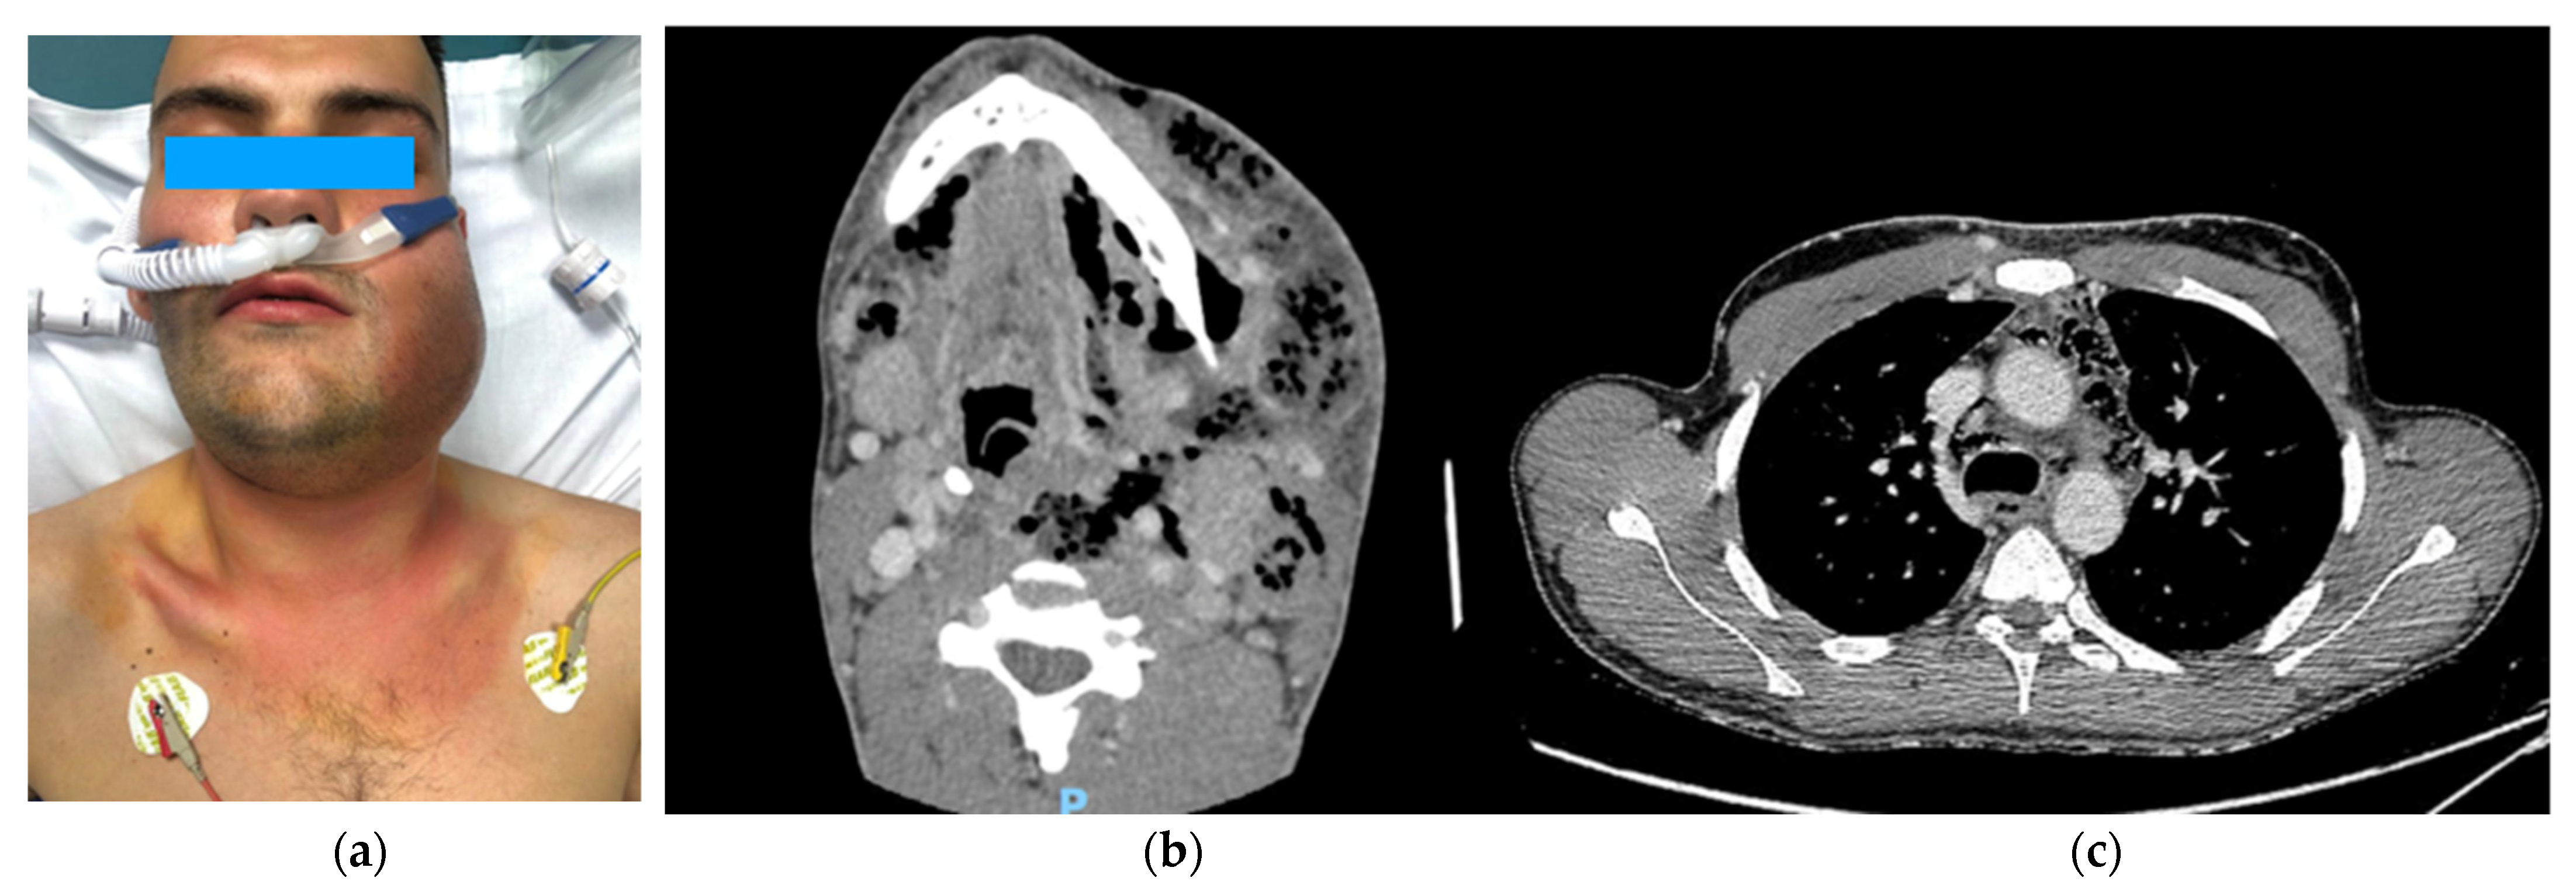

The first was a 36-year-old male who had a left third mandibular molar odontectomy 5 days before the evidence of cheek swelling and pain. He went to another hospital where he was discharged with a prescription for antibiotics and corticosteroids. The day after, he went to our Emergency Department with a voluminous left face swelling and subcutaneous crackling with fever and confusion (Figure 2). After neck and thorax CT scan were performed, the patient was transferred to the operating room for drainage of cervical abscess and insertion of two transcervical drainages, one into the anterior and one into the posterior mediastinum. The cervical wound was kept open and packed to permit daily irrigation with iodopovidone and saline solution. One week later, for worsening clinical conditions, with the onset of pleural and pericardial effusion, the patient underwent subxiphoid pericardial drainage, right thoracotomy and insertion of three pleural tubes, and a second cervicotomy. Seven days later, the patient went again to the operating room for a second right thoracotomy and left thoracoscopy for the onset of purulent fluid collections in the aorto-pulmonary window, close to the subclavian artery and along the left pericardium. After this bilateral operation, the patient’s conditions improved, and he was discharged on postoperative day 36 without sequelae.

Figure 2.

(a) A 36-year-old man with cheek swelling after tooth extraction. (b) A preoperative computed tomography scan showing a voluminous collection with hypodense material, multiple sepiments, and an extensive aerial component in the context at the epicenter in the left tonsillar loggia. (c) A mediastinal abscess with gas pocket formation in the anterior mediastinum and around the trachea.